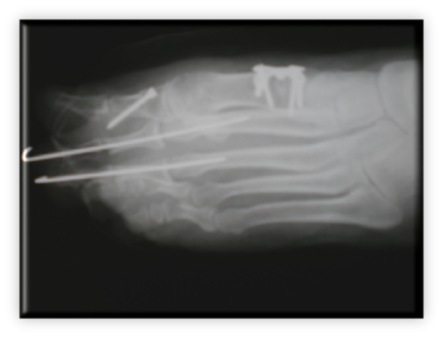

Πρόκειται για σύνθετη παθολογία του μεγάλου δακτύλου του ποδιού, που εκτός από την παραμόρφωση σε βλαισσότητα, όπως το όνομα υποδηλώνει, συνυπάρχει στροφική παραμόρφωση και γενικότερα παραμόρφωση ολόκληρου του πρώτου στοίχου (ταρσός, μετατάρσιο, δάκτυλο) αλλά και των μικρότερων δακτύλων. Πιο συγκεκριμένα, υπάρχουν οστεόφυτα στις αρθρώσεις και κυρίως στην έσω επιφάνεια της κεφαλής του πρώτου μεταταρσίου (κότσι), τροφικές αλλοιώσεις του δέρματος και δερματικοί κάλοι στα σημεία αυξημένης φόρτισης, λέπτυνση του υποδορίου λίπους στην πελματιαία επιφάνεια, εξάρθρημα σησαμοειδών οσταρίων, ανισορροπία στους άξονες έλξης των τενόντων περί του μεγάλου δακτύλου, υμενίτιδα στην έσω επιφάνεια της μεταταρσιοφαλλαγγικής η οποία είναι και πολύ επίπονη. Εμβιομηχανικά ο άξονας φόρτισης του ποδιού μεταφέρεται στο διάστημα μεταξύ πρώτου και δεύτερου στοίχου με αποτέλεσμα το πρώτο μετατάρσιο να δέχεται λιγότερα φορτία από όσο θα έπρεπε και τελικώς μεταταρσιαλγία στις κεφαλές των μικρότερων μεταταρσίων, παραμορφώσεις των μικρότερων δακτύλων με συχνότερη αυτή του δευτέρου που καταλήγει σε γαμψοδακτυλία, εφίππευση επί του πρώτου, στεόφυτα και δερματικό κάλο στην ραχιαία επιφάνεια της πρώτης φαλαγγοφαλαγγικής άρθρωσης, οστεοχόνδρινες αλλοιώσεις των αρθρώσεων και τελικά αρθρίτιδα.

ΒΛΑΙΣΟΣ ΜΕΓΑΛΟΣ ΔΑΚΤΥΛΟΣ (HALLUX VALGUS)

Στις ακτινογραφίες πρέπει να μετρηθούν η γωνία μεταξύ 1ου και 2ου μεταταρσίων με ανώτερα όρια 8-9 μοίρες, η γωνία βλαισσότητας του 1ου μεταταρσίου και 1ης φάλαγγας που όταν ξεπερνά τις 15 μοίρες ορίζεται παθολογική. Συμπληρωματικά μπορούν να μετρηθούν οι γωνίες προσανατολισμού της αρθρικής επιφάνειας κεφαλής 1ου μεταταρσίου και η γωνία προσανατολισμού κεντρικής αρθρικής επιφάνειας 1ης φάλαγγας του μεγάλου δακτύλου.

Ο κατάλληλος χρόνος χειρουργικής αντιμετώπισης είναι εξειδικευμένος για κάθε περιστατικό, λαμβάνοντας υπόψη την ύπαρξη όλων των ανωτέρω παραμέτρων και την επίδραση που έχουν στη λειτουργικότητα αλλά και αισθητική του άκρου ποδός. Γενικότερα η επέμβαση δεν είναι απαραίτητο να γίνεται υπερβολικά νωρίς απλά και μόνο επειδή κάποιες γωνίες στις ακτινογραφίες είναι πάνω από το φυσιολογικό, αλλά ούτε και υπερβολικά καθυστερημένα  καθιστώντας το χειρουργείο πραγματική πρόκληση από τεχνική άποψη. Περιγράφονται περί τα 150 είδη επεμβάσεων για τη συγκεκριμένη παθολογία και τις παραλλαγές της. Είναι έργο του χειρουργού σε πλήρη συνεργασία με τον ασθενή να επιλεγεί η κατάλληλη επέμβαση για τον κατάλληλο ασθενή στον κατάλληλο χρόνο. Περιγράφονται επεμβάσεις από τις πιο απλές, συνθετότερες με τεχνικές ελάχιστης επεμβατικότητας έως και πολύ σύνθετες.